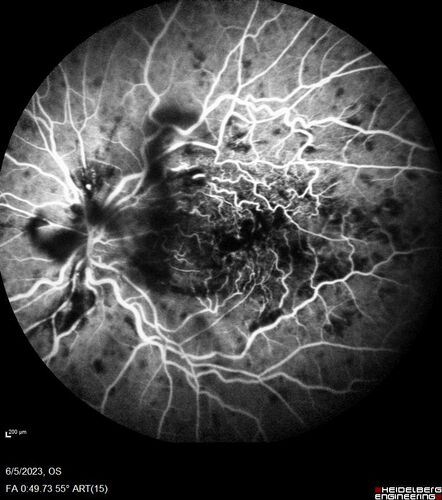

central retinal vein occlusion - a lot of hemorrhage - on coumadin

84 year old man with severe vision loss left eye for 2 weeks. VA 5/200 OS - Patient on Warfarin for valve replacement.

CRVO with Edema - Hemorrhage on Warfarin